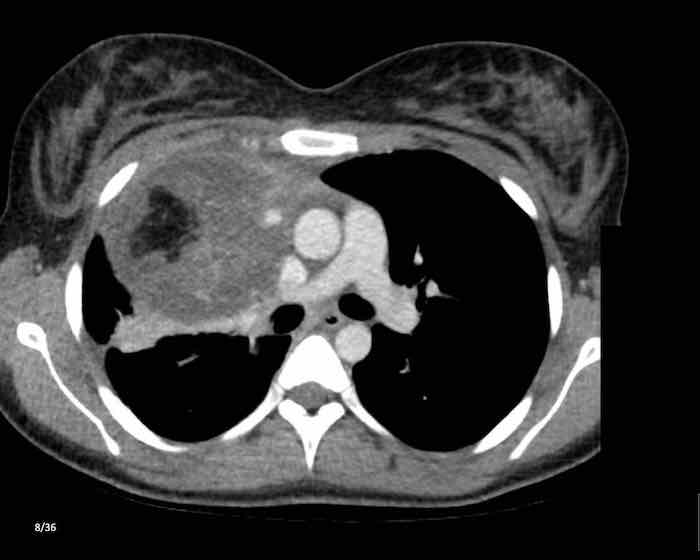

Các hình ảnh này của một nam giới 71 tuổi.

Trên CT ngực, tình cờ phát hiện một khối ở tuyến ức.

Hãy phân tích các hình ảnh. Nhận định của bạn là gì?

Hình ảnh

Một phần tổn thương có ngấm thuốc cản quang và có một số vôi hóa, có thể nằm ở thành nang.

Khi một tổn thương tuyến ức có thành phần đặc, nguyên tắc là… “khi còn nghi ngờ, hãy phẫu thuật cắt bỏ”.

Tổn thương đã được phẫu thuật cắt bỏ dựa trên kết quả CT và kết quả giải phẫu bệnh cho thấy đây là u tuyến ức dạng nang.